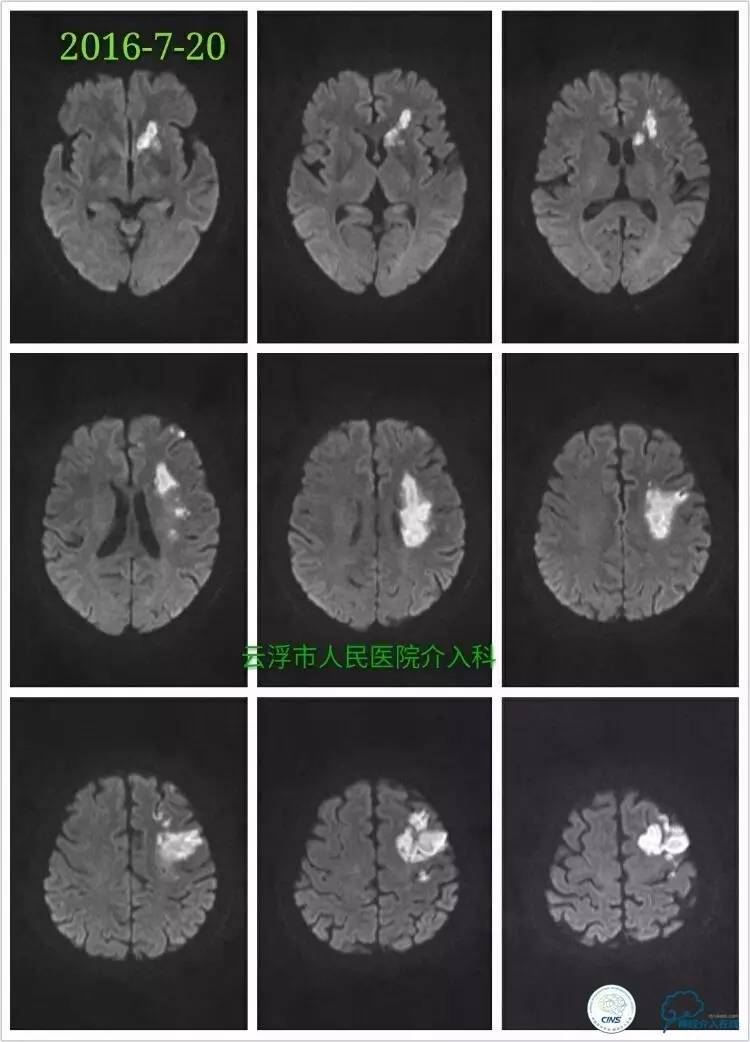

》2016-7-20

颅脑MRA检查:左侧额颞叶、基底节区、放射冠区急性脑梗塞,左侧颈内动脉颅内段重度狭窄。